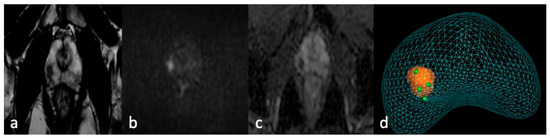

Before the procedure, mpMRIs were evaluated using software (ProMap Lite™ (Version 2024), KOELIS, Meylan, France) dedicated to 3D lesion semiautomatic segmentation on high-resolution T2-weighted images (Figure 1).

Figure 1. MRI-TBx procedure. Apex right PZpl prostate lesion at mpMRI (PI-RADS 4): (a) MRI-T2 image; (b) MRI-DWI image; (c) MRI-ADC image; (d) MRI-targeted biopsy report.